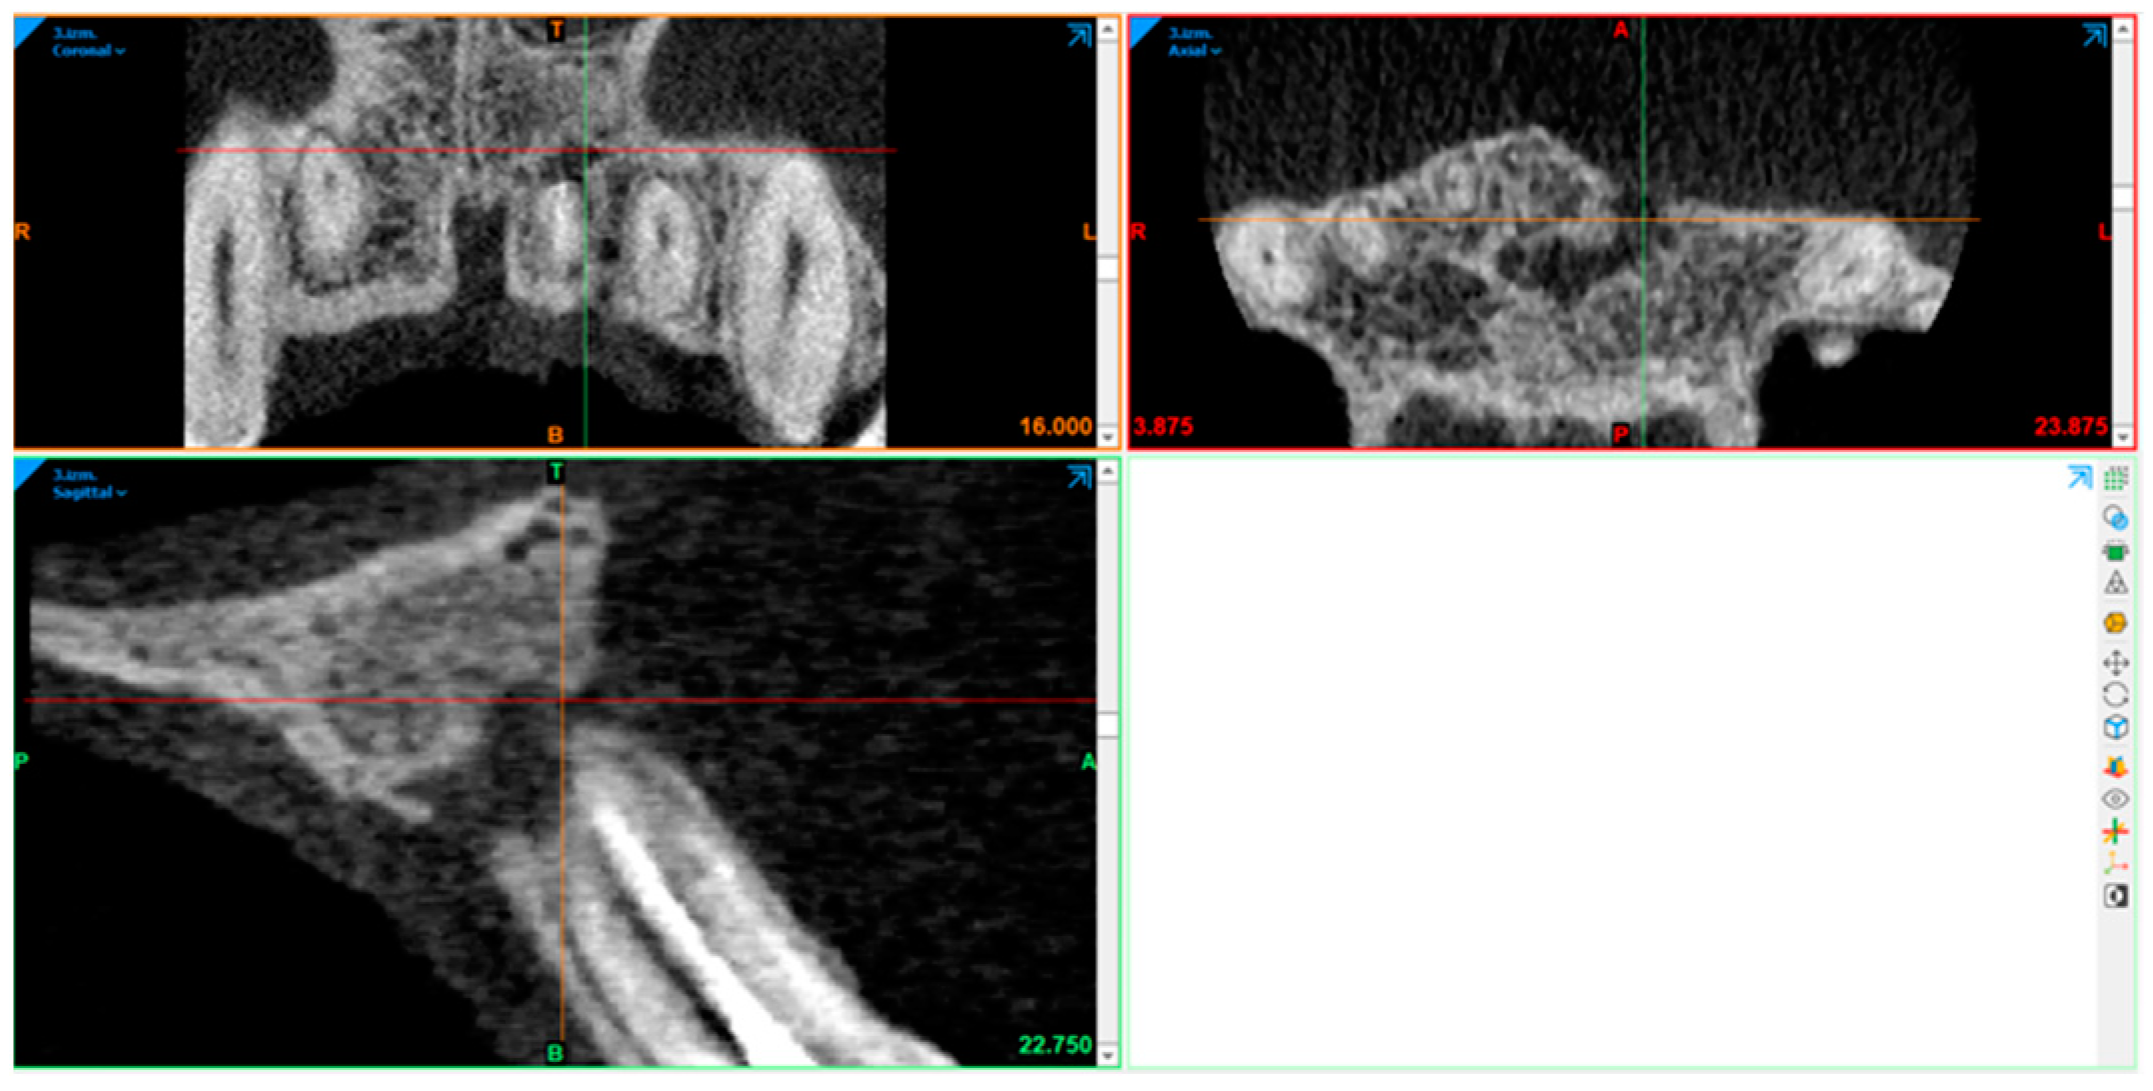

2.10. Radiography Acquisition: Volumetric Assessment

2.11. Statistical Analysis